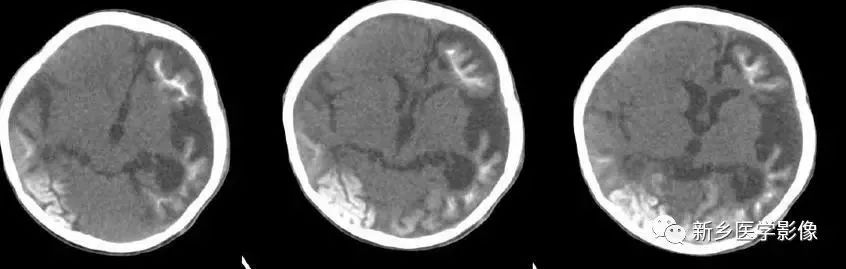

- Huntington's 病(亨廷顿舞蹈症):是一种常染色体显性遗传的、基底节和大脑皮层变性性疾病,主要损害基底节和大脑皮层,尾状核、壳核病变最明显。病理表现为:小神经节细胞严重破坏,大细胞也减少、尼氏体消失、核固缩、出现类淀粉小体,还有脱髓鞘改变和胶质增生,基底节部受累常最明显且发生最早。临床主要根据3大特征:舞蹈样动作、痴呆、家族史诊断。